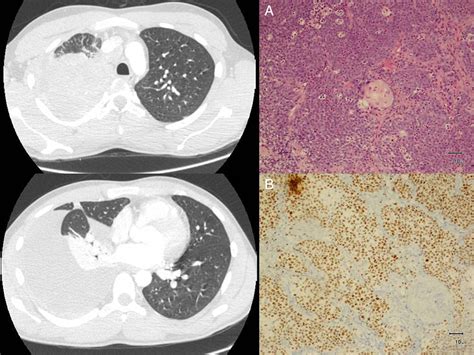

Once a clinical suspicion arises, a definitive diagnosis is paramount. The diagnostic journey usually involves a combination of imaging and tissue biopsy. Below is a summary of the diagnostic tools typically utilized in the clinical setting:

Diagnostic Tool Purpose in NMC Evaluation

CT and PET Scans Identifying the primary tumor site and assessing for metastatic spread.

Core Needle Biopsy Obtaining a sample of the tumor for pathological review.

IHC Staining Detecting the expression of the NUT protein within the biopsy sample.

Molecular Testing (FISH) Confirming the specific NUTM1 gene translocation.